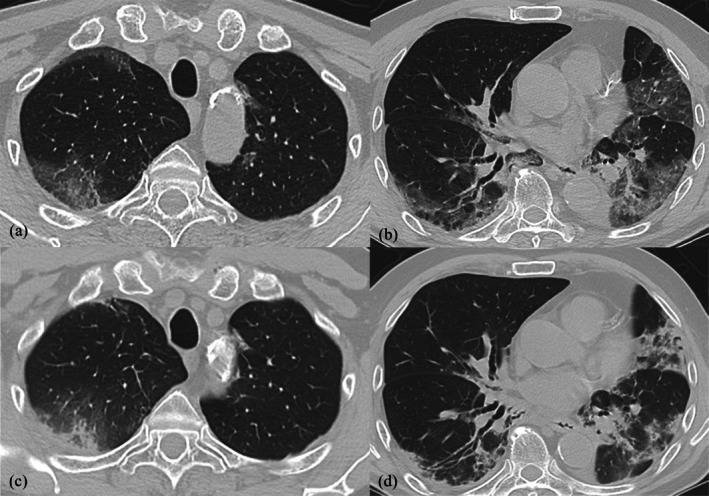

Regorafenib是一种多靶点酪氨酸激酶抑制剂(TKI),适用于难治性结直肠癌、胃肠道间质瘤(GIST)和肝细胞癌(HCC)。我们报告一例66岁男性顽固性结直肠癌患者,由于瑞非尼治疗而发展为间质性肺炎。开始瑞非尼治疗3个月后,胸部计算机断层扫描显示双侧磨玻璃混浊,这是间质性肺疾病的特征性发现。本病例显示瑞非尼诱发的间质性肺疾病在影像学表现后进展相对较快。临床医生应该对接受瑞非尼治疗的患者的潜在肺毒性保持警惕,即使治疗开始后潜伏期明显较短。早期识别和及时干预是处理这一不良事件的关键。

Regorafenib, a multi-targeted tyrosine kinase inhibitor (TKI), is indicated for refractory colorectal carcinoma, gastrointestinal stromal tumours (GIST), and hepatocellular carcinoma (HCC). We present a case involving a 66-year-old male patient with refractory colorectal cancer who developed interstitial pneumonia as a consequence of regorafenib therapy. Three months following the initiation of regorafenib administration, a chest computed tomography scan revealed bilateral ground-glass opacities, a characteristic finding in interstitial lung disease. This case illustrates a relatively rapid progression of regorafenib-induced interstitial lung disease following its radiographic manifestation. Clinicians should remain vigilant for this potential pulmonary toxicity in patients receiving regorafenib, even with an apparently short latency period after treatment commencement. Early recognition and prompt intervention are crucial in managing this adverse event.